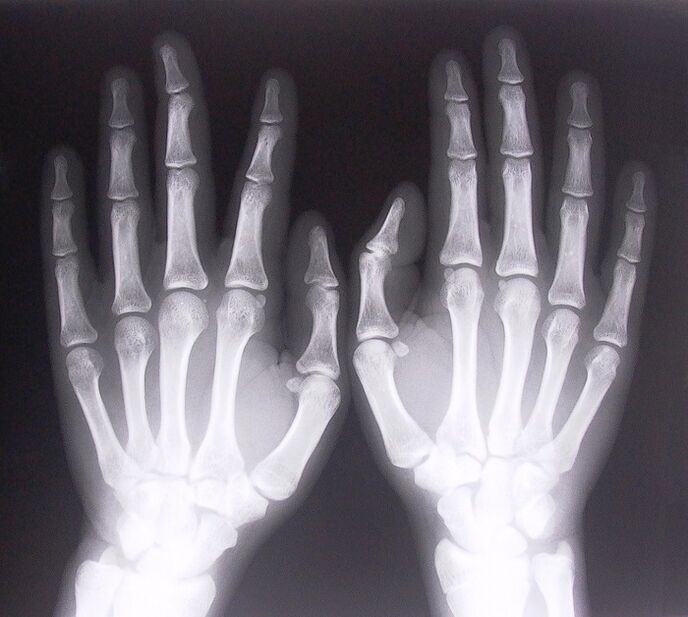

- Стенозиращ лигаментит. За да се определи причината за заболяването, е необходимо да се подложи на рентгеново изследване. Симптомите са типични: болезнено движение на ръката, примка на стиснатата длан. Освен това по време на удължаване обикновено се чуват щраквания.

За да започнете да лекувате болки в ставите на пръстите, трябва правилно да определите какво заболяване ги е причинило. За да се определи какъв вид заболяване засяга човек, който изпитва болка в ставите при огъване на ръцете си, лекарите препоръчват да се подложат на следните процедури:

- Направете рентгенови снимки.